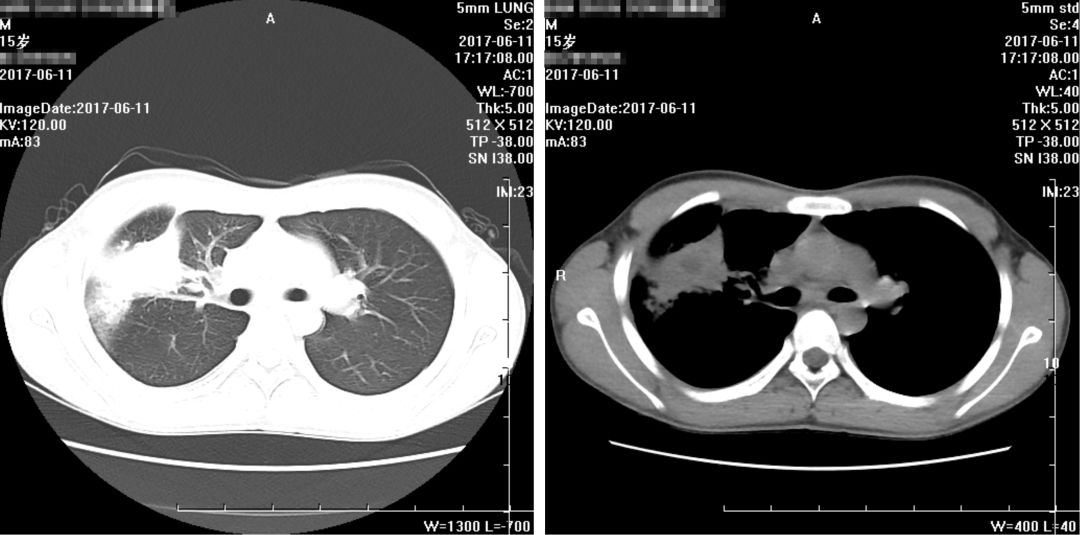

入院CT报告(2017-06-11):

1、右肺上叶-中叶见团块状软组织密度影,周边可见磨玻璃密度影,病变大小约5.08*3.38cm,CT值约25HU,其内密度不均,中心可见低密度影,CT值约5HU,病变与胸膜宽基底相连,与右侧横膈胸膜分界不清,建议增强进一步检查。

2、右肺上叶前段支气管欠通畅,建议复查。

3、右肺上叶、中叶、下叶内基底段条索

4、右侧胸膜增厚,右侧少许胸腔积液

5、纵隔内、两侧腋窝下小淋巴结,前纵隔软组织密度影,考虑未退化完全胸腺组织。

复查胸部CT报告:

1、右肺病变较前略有变化,部分减轻,尖段病变增多,请结合病原学检查;

2、右侧少许胸腔积液基本吸收;

3、纵隔及两侧腋窝多发淋巴结部分稍增大,较前未见明显变化。

余大致同前。

(2017年6月11日)

(2017年6月22日)